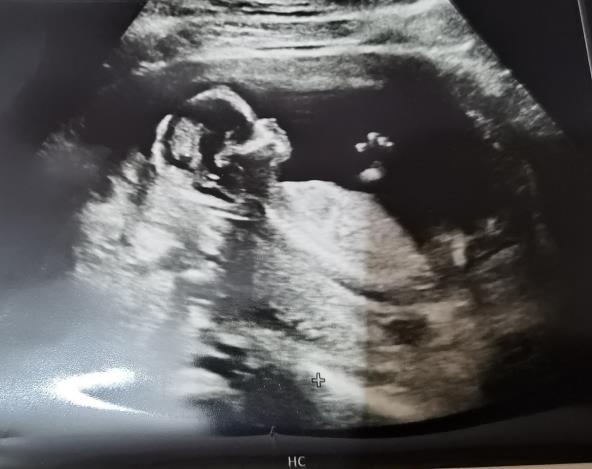

Svaki budući roditelj jedva čeka da čuje vest kog pola je beba koju očekuje. Iako postoje brojne teorije koje mogu i pre ultrazvuka da otkriju da li čekate dečaka ili devojčicu, uvek ih treba uzeti sa dozom rezerve, pa čak iako pokažu tačan rezultat. I pored brojnih nepouzdanih, pojavila se jedna jako zanimljiva "teorija lobanje". Zapravo ona vam omogućava da odredite pol bebe na osnovu oblika glave sa ultrazvuka.

Da biste to pokušali sve što vam treba je slika sa ultrazvuka rađena u 12 nedelji, lupa i informacije po čemu se razlikuje oblik i veličina glave:

Kod dečaka:

• čelo je niže i nagnutije

• vrh glave je kockastiji i veći

• jagodice su izraženije

• obilk kostiju glave je kvadratni

Kod devojčica:

• vrh glave je okrugliji i sužava se na vrhu

• jagodice su manje izražene

• kosti glave su zaobljenije

• čelo je više i manje nagnuto

Mnogi pomenuti metod otkrivanja pola hvale i tvrde da je efikasan čak 92 odsto, međutim ima i onih koji su skeptični. Ginekolog Shazia Malik ističe da ne postoji " značajni naučni dokaz da je teorija lobanje pouzdana, ali ne može da šteti bebi ni na koj način pa može da bude zanimljiva smernica budućim roditeljima prilikom nagađanja."